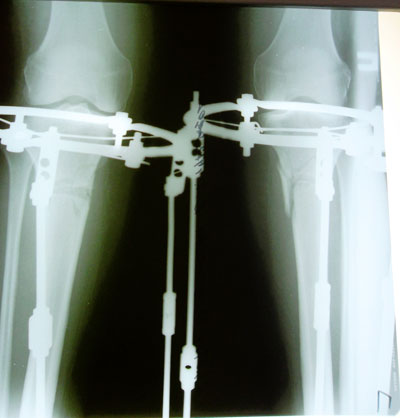

Дата операции 01.07.2014г.

Внутренний контур голеней слабо выражен или практически отсутствует.